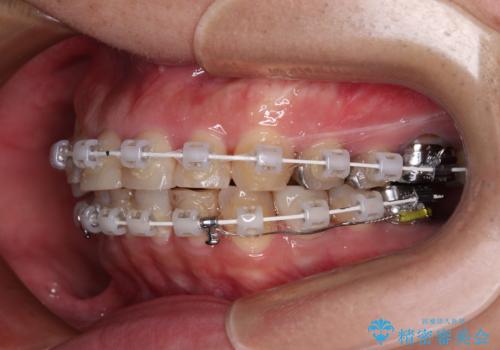

抜歯が必要な歯は事前に抜歯をし、その後ワイヤー装置にて歯列矯正を行い、途中でインプラントを埋入し、オールセラミッククラウンにて補綴治療を行うこととしました。

矯正治療にやや時間がかかりましたが、歯列はきれいに整い、気になっていたむし歯や銀歯は自然な色合いに仕上がりました。